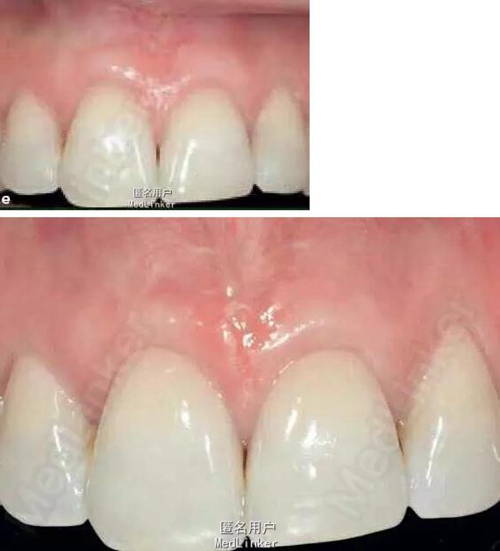

48歲女性,上中切牙牙齦退縮,要求解決美觀問(wèn)題

右上中切牙有4mm牙齦退縮,左上中切牙有2mm牙齦退縮,牙根暴露

診斷:牙齦退群 治療:牙齦美學(xué)修復(fù) 圖2在唇系帶旁做直達(dá)骨膜下的隧道式切口,從中切牙的齦溝到膜齦聯(lián)合全程剝離以利于牙齦冠向復(fù)位時(shí)釋放壓力 圖3在隧道內(nèi)放入可吸收的膠原膜,冠向復(fù)位齦緣,并用縫線固定齦緣及里面的膠原膜,然后再將縫線打結(jié),結(jié)頭用復(fù)合樹(shù)脂粘接在牙冠中1/3。 圖4正中的切口位置和壓力接近,用6個(gè)0縫線縫合。

術(shù)后三周拆線,下圖分別為術(shù)后12個(gè)月后及術(shù)后35個(gè)月后,效果非常好,患者非常滿(mǎn)意